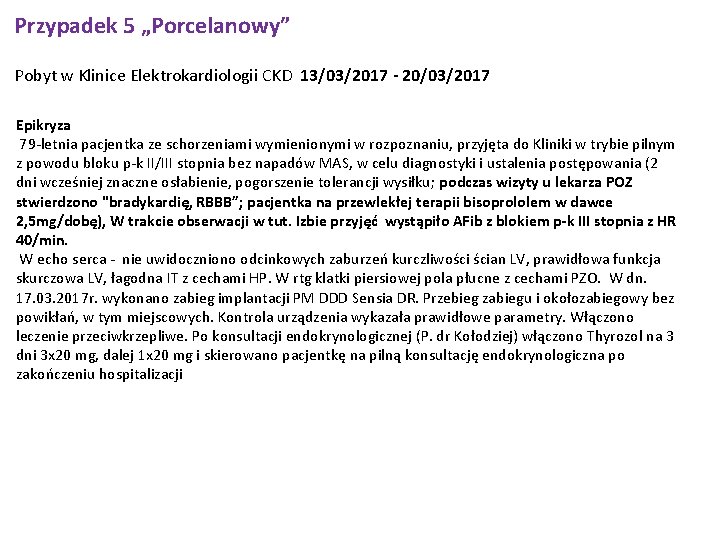

Przypadek 5 „Porcelanowy” Pobyt w Klinice Elektrokardiologii CKD 13/03/2017 - 20/03/2017 Epikryza 79 -letnia pacjentka ze schorzeniami wymienionymi w rozpoznaniu, przyjęta do Kliniki w trybie pilnym z powodu bloku p-k II/III stopnia bez napadów MAS, w celu diagnostyki i ustalenia postępowania (2 dni wcześniej znaczne osłabienie, pogorszenie tolerancji wysiłku; podczas wizyty u lekarza POZ stwierdzono "bradykardię, RBBB”; pacjentka na przewlekłej terapii bisoprololem w dawce 2, 5 mg/dobę), W trakcie obserwacji w tut. Izbie przyjęć wystąpiło AFib z blokiem p-k III stopnia z HR 40/min. W echo serca - nie uwidoczniono odcinkowych zaburzeń kurczliwości ścian LV, prawidłowa funkcja skurczowa LV, łagodna IT z cechami HP. W rtg klatki piersiowej pola płucne z cechami PZO. W dn. 17. 03. 2017 r. wykonano zabieg implantacji PM DDD Sensia DR. Przebieg zabiegu i okołozabiegowy bez powikłań, w tym miejscowych. Kontrola urządzenia wykazała prawidłowe parametry. Włączono leczenie przeciwkrzepliwe. Po konsultacji endokrynologicznej (P. dr Kołodziej) włączono Thyrozol na 3 dni 3 x 20 mg, dalej 1 x 20 mg i skierowano pacjentkę na pilną konsultację endokrynologiczna po zakończeniu hospitalizacji

Przypadek 5 13. 11. 2017 Wykonano nakłucie jamy opłucnowej - pobrano łącznie około 100 militrów jasnożółtego, przejrzystego płynu do badan. Nakłucie przerwano w związku z brakiem wypływu dalszej ilości płynu. Po nakłuciu pacjentka w stanie ogólnym dobrym, dolegliwości nie zgłasza. Osłuchowo szmer pęcherzykowy prawidłowy, medpedia. framar. bg

Przypadek 5 RTG klatki piersiowej PA i bok. 13. 11. 2017 Stan po nakłuciu prawej jamy opłucnej - cech odmy opłucnowej nie stw. się. W por. do bad. poprz. z dn. 09. 11. 2017 r - regresja ilości płynu w prawej jamie opłucnej - aktualnie sięga przedniego odc. żebra VI; po stronie lewej płyn spłycający kąt p-ż; obustronnie, nad poziomem płynu zmiany niedodmowe/niedodmowo-zapalne. Drobne zmiany guzkowo-włókniste w szczycie lewego płuca. Poza tym pola płucne bez zmian ogniskowych, o cechach niewydolności w krążeniu płucnym. Wnęki płucne poszerzeone, najpewniej naczyniowo. Ocena sylwetki serca utrudniona - wydaje się być powiększona. Aorta piersiowa w normie. Zmiany zwyr. kręgosłupa Th. Stan po implantacji kardiostymulatora 2 elektrodowego; końcówki elektrod rzutują się w PP i PK ; ciągłość elektrod zachowana;

Przypadek 5 Przed Po

Przypadek 5 W trakcie pobytu włączono leczenie moczopędne, wykonano diagnostyczne nakłucie jamy opłucnowej prawej w którym odbarczono ok. 100 ml jasnożółtego, przejrzystego płynu. W badaniu cytologicznym wykryto komórki atypowe, prawdopodobnie nowotworowe ("cellulae atypicae, probaliter carcinomatosae" - prof dr hab n. med. Marian Danielewicz).